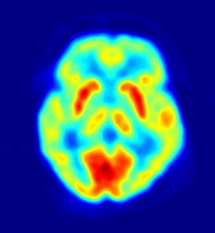

Resultados de una TEP. Fuente: Wikimedia Commons.

Actualmente, los diagnósticos completamente concluyentes de la enfermedad del Alzheimer sólo se pueden hacer a través de exámenes cerebrales post-mortem. En vida, los especialistas diagnostican la enfermedad gracias a una técnica denominada tomografía por emisión de positrones (TEP).

La TEP es una técnica no invasiva con la que se puede medir la actividad metabólica de los diferentes tejidos del cuerpo humano. Está basada en detectar y analizar la distribución que adopta en el interior del cuerpo un trazador o radioisótopo (variante de un elemento cuya energía puede detectarse), administrado a través de una inyección.

El trazador utilizado por los científicos en este caso fue el compuesto Pittsburg B (PiB), capaz de revelar la presencia de las placas amiloides, cuya aparición supone un cambio en el cerebro que numerosos neurólogos han relacionado con el desarrollo del Alzheimer.